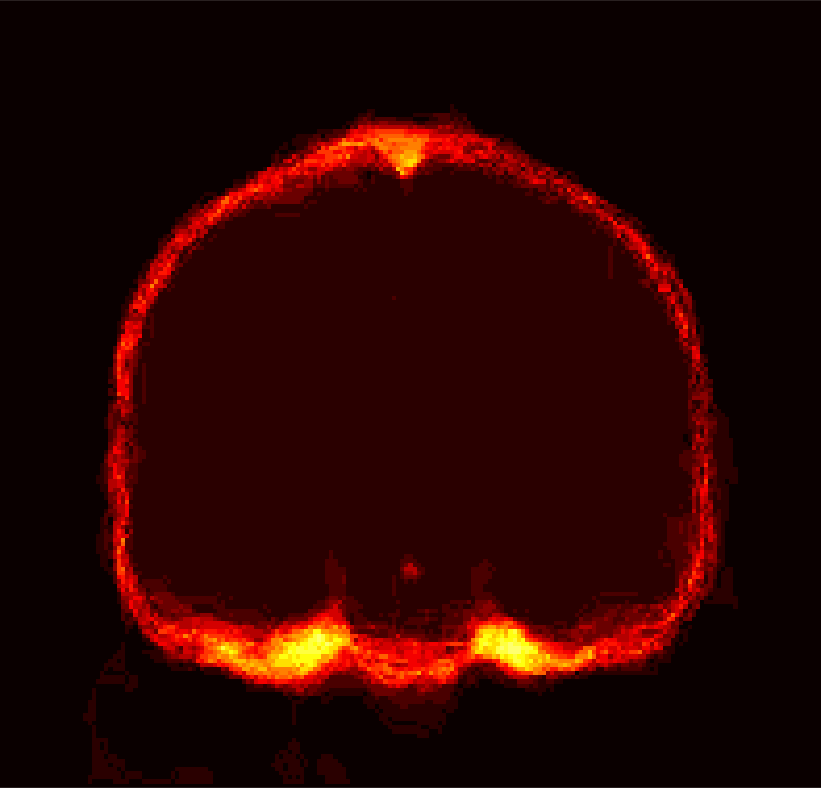

Fig. 1 shows example images from each dataset to illustrate image variability. IBSR and LPBA40 contain images from normal subjects and include large portions of the neck; BRATS has very low out-of-plane resolution; and the TBI dataset contains large pathologies and abnormal skulls.

Refer to caption

Figure 1: Illustration of image appearance variability on a selection of images from each (evaluation) database. From top to bottom: IBSR, LPBA40, BRATS and TBI.